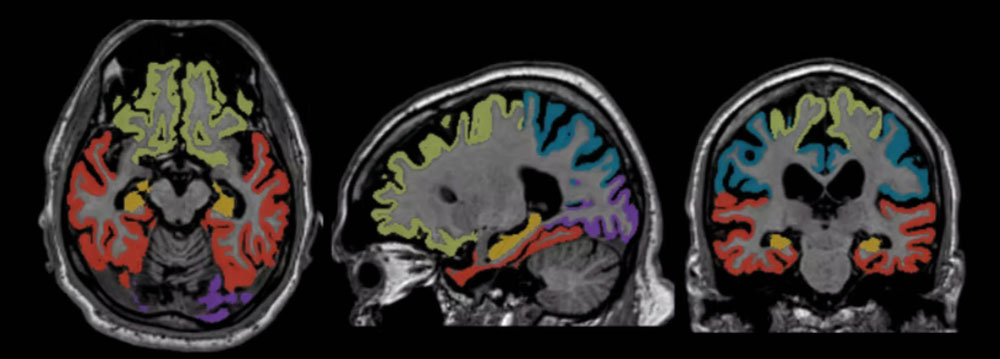

Icobrain è un software medico certificato che utilizza algoritmi avanzati di intelligenza artificiale per analizzare le immagini cerebrali ottenute tramite Risonanza Magnetica e Tomografia Computerizzata. Il suo compito non è sostituire il medico, ma fornire una valutazione quantitativa estremamente precisa del volume del cervello e delle sue principali strutture. Oggi se ne parla molto perché rappresenta uno degli strumenti più innovativi nel supporto alla diagnosi precoce e al monitoraggio di patologie neurodegenerative, come le demenze e la sclerosi multipla.

Nel caso delle demenze, la capacità di calcolare con precisione i volumi cerebrali e l’atrofia delle diverse aree del cervello è cruciale. I cambiamenti strutturali legati al deterioramento cognitivo, infatti, possono essere minimi all’inizio e difficili da rilevare a occhio nudo. Icobrain fornisce numeri, percentuali e confronti rispetto a valori normativi della popolazione, rendendo più semplice individuare segni precoci di atrofia e monitorarne l’evoluzione nel tempo.